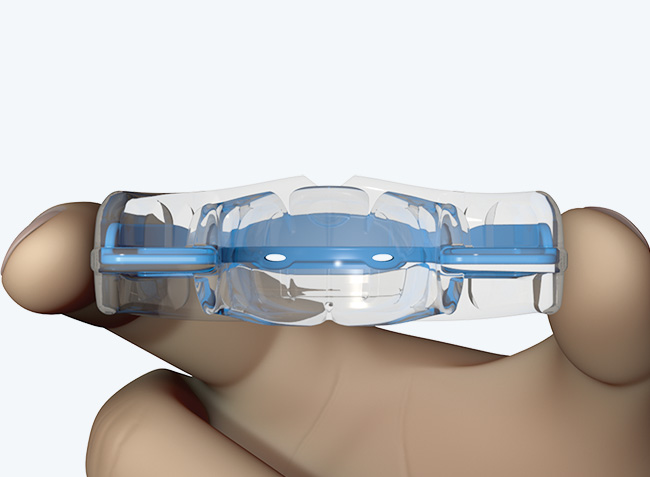

myobrace Medium Myobrace Orthodontic Teeth Trainer Appliance T1, Medium andの詳細情報

Myobrace Orthodontic Teeth Trainer Appliance T1, Medium and。S1。T3。子どもが使用しました。寝るときだけでも効果はあります。お試ししたい方へ。。T3。ポンちゃんです(他の方は購入出来ません)。SE11L ハンドピース OSADA オサダ